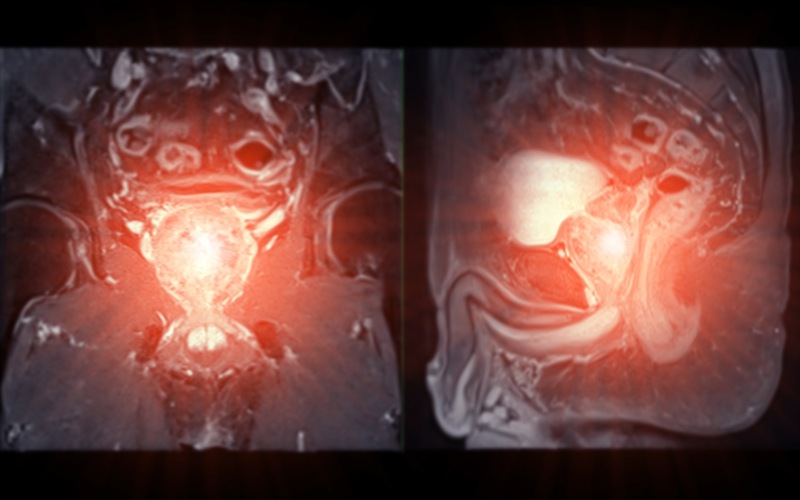

Nang tuyến tiền liệt là một bệnh lý hiếm gặp của tuyến tiền liệt, với tỷ lệ mắc bệnh dao động từ 0,5% – 7,9%. Bệnh thường không bộc lộ triệu chứng, chỉ được phát hiện tình cờ khi thăm khám sức khỏe thông qua chẩn đoán hình ảnh như siêu âm bụng, chụp cắt lớp vi tính (CT) hoặc chụp cộng hưởng từ (MRI). (3)